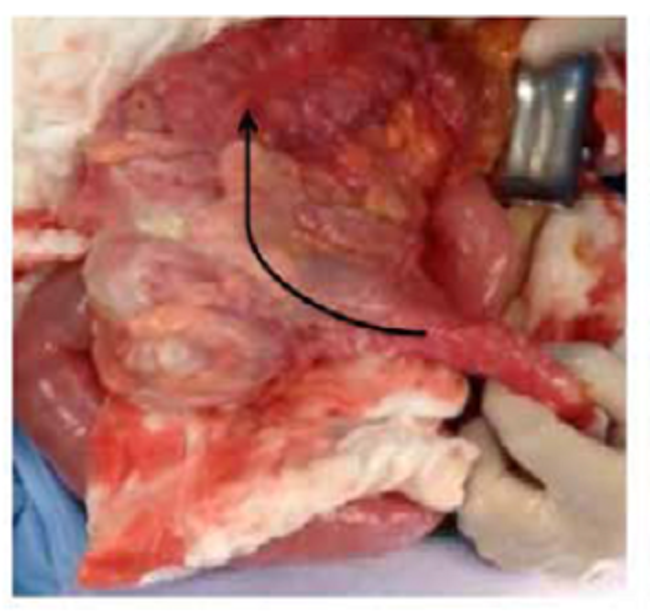

En la laparotomía exploratoria se encontró una intususcepción del colon derecho, que atravesaba el colon transverso y alcanzaba parte del colon descendente (figura 2). Tras la reducción manual, se palpó una masa bien delimitada, de 5 cm de diámetro, en el colon transverso. Se practicaron una hemicolectomía derecha con principios oncológicos y una anastomosis ileocólica. El periodo posoperatorio transcurrió sin complicaciones y el paciente fue dado de alta a los cinco días de la intervención. El examen histopatológico del colon resecado reveló una masa de 2 x 5 cm correspondiente a un adenocarcinoma mucinoso (figura 3).

Por persistencia del dolor abdominal, se decidió practicar una laparotomía exploratoria, en la que se encontró una intususcepción ileocólica (figura 5). Tras la reducción manual, se visualizó una masa de 6 cm de diámetro, aproximadamente, en la válvula ileocecal. Se optó por una hemicolectomía oncológica derecha y anastomosis ileocólica. El periodo posoperatorio transcurrió sin complicaciones y el paciente fue dado de alta a los siete días de la intervención. El examen histopatológico de la pieza quirúrgica reveló una masa de 4 x 6 cm correspondiente a un tumor del estroma gastrointestinal (GIST) (figura 6).